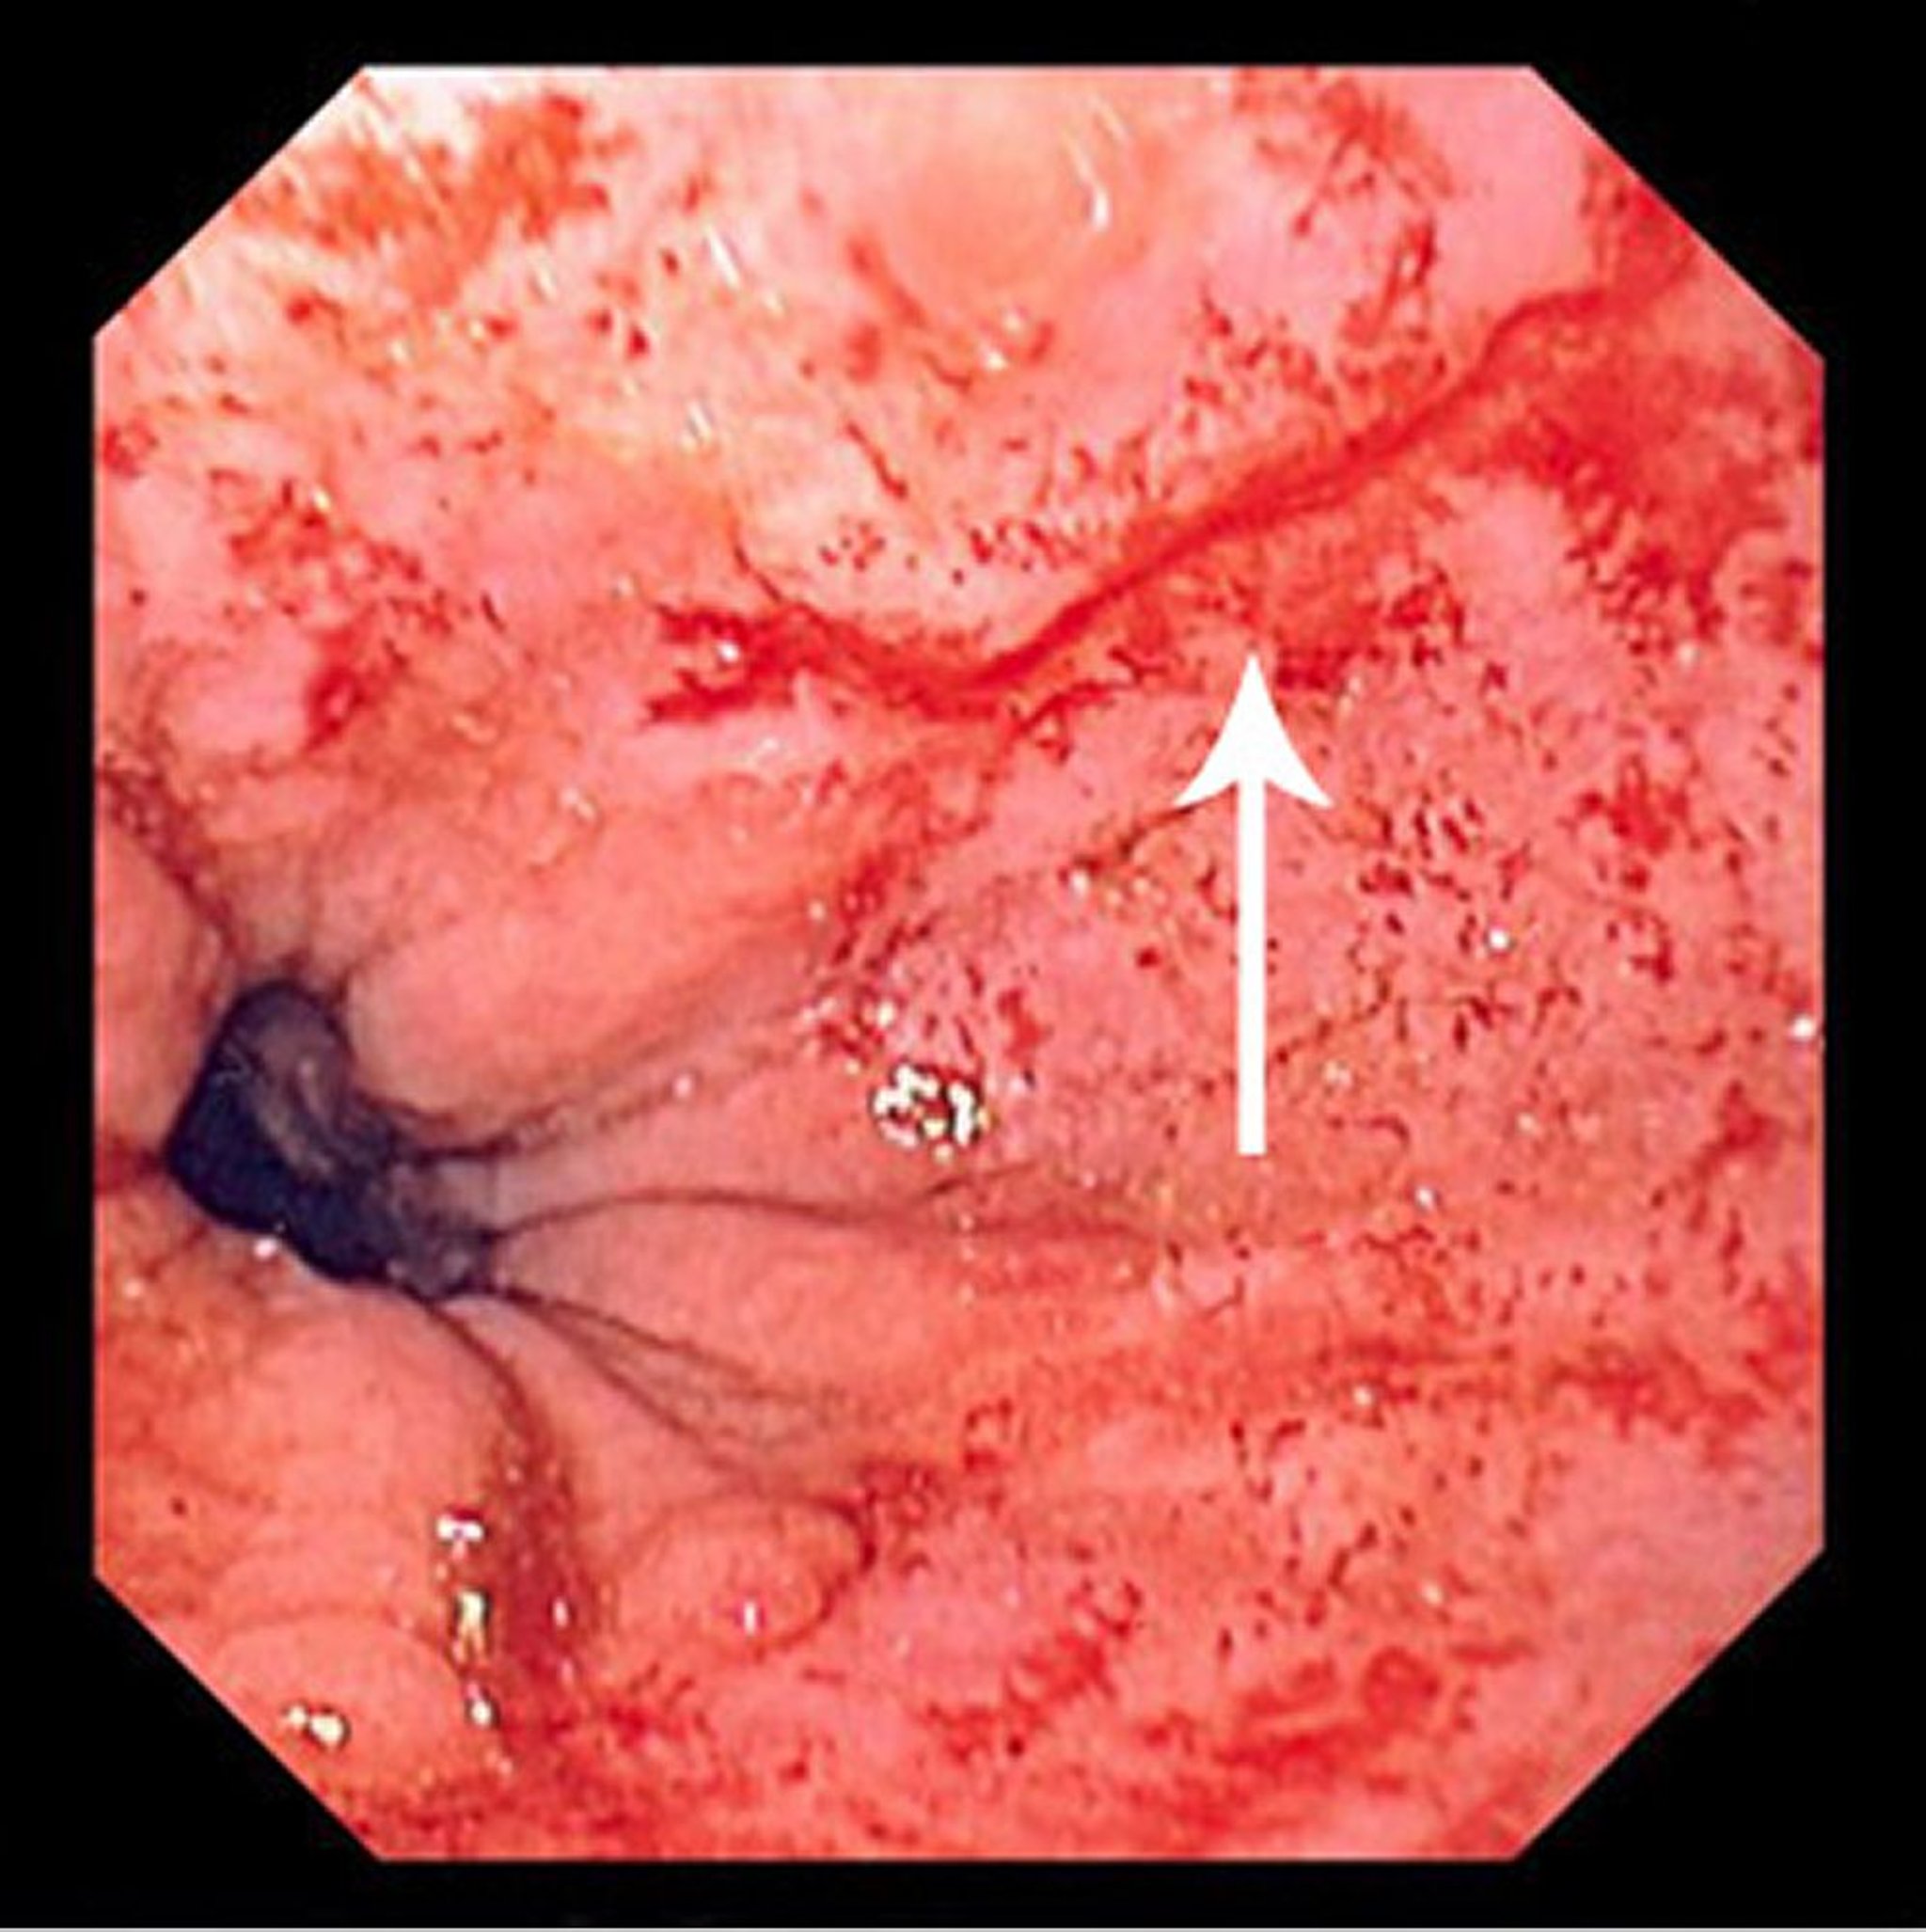

This image shows a thin, linear tear (arrow) beginning just above the squamocolumnar junction and extending proximally.

Image provided by David M. Martin, MD.